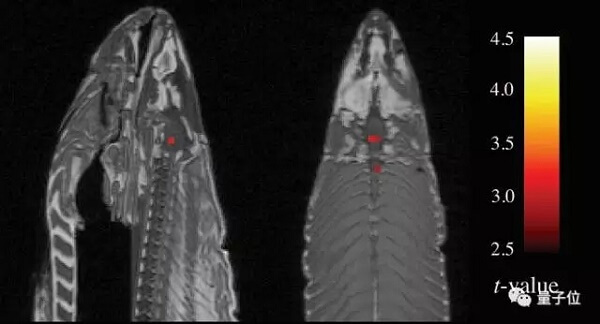

AI只花了几分钟时间,就根据任务对亚当提出的两个大脑网络的激活情况,选出了一些任务。这两个大脑网络,就是我们前文提到的演绎推理和空间工作记忆。

5月的一个上午,这个团队重复了原来的实验,他们的葡萄牙同事伊内斯(Ines Violante)勇敢地躺在扫描器巨大磁铁中间的洞里。几分钟后,罗米拿了一份图表给我看,上面展示了伊内斯做每个测试时,不同大脑网络的激活情况。

那份图表,看起来就像一幅马克·罗斯科的画,颜色鲜艳。红色,表示两个回路中的活动没有顺利衔接,蓝色,表示他们连接得很好。

在图表的右下角,有一个红色的菱形,表示两个测试利用了两个相互独立的回路:演绎推理和空间工作记忆。里奇笑着说,这很好地复现了之前试用的情况。